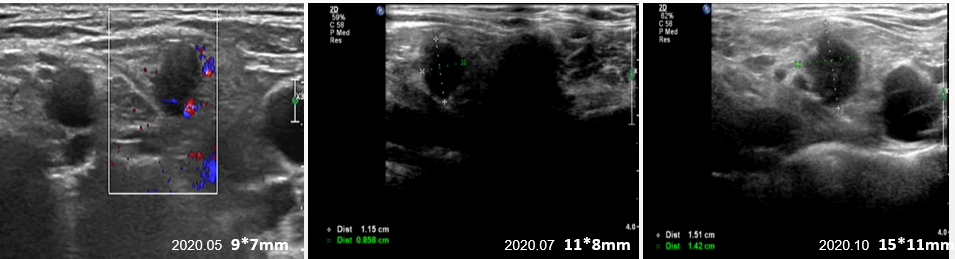

继续维持上述方案两个疗程后,停静脉化疗,改口服化疗维持,即:原研曲妥珠单抗300mg Q3W+吡咯替尼320mg QD+卡培他滨1.0g BID+唑来膦酸4mg Q4W。维持至2020.05复查出现右侧锁骨上淋巴结,考虑转移,评估PD,PFS 16个月。

建议干预,患者要求考虑并继续维持方案:曲妥珠单抗300mg Q3W+吡咯替尼320mg QD+卡培他滨1.0g BID+唑来膦酸4mg Q4W。维持至2020.10,右锁骨上LN进行性增大,余未见异常(图4)。

图4. 右侧锁骨上淋巴结回声影像图